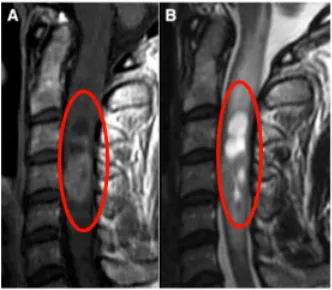

手术非常成功,术后12天复查时证实,肿瘤已得到全部切除,且术后水肿几乎完全消失,术前的颈椎疼痛也慢慢消失。术后两周礼小姐顺利出院,术后一个月,恢复迅速的她再次回归正常的生活。